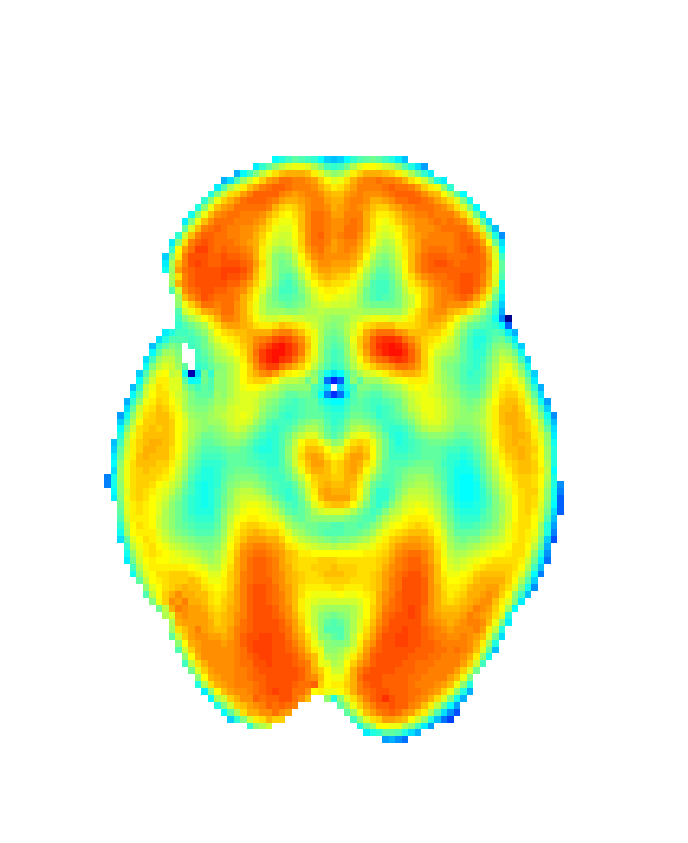

First, images used in biomedical studies are often irregularly shaped, which implies a need for reliable smoothing methods. However, such methods usually suffer from a problem of leakage with complex data structures such as the ones here considered, showing difficulties in the estimation for boundary regions. With our FDA approach, this problem is addressed by applying bivariate splines over Delaunay triangulations [61], thus preserving the features of these complex brain images [62] (see Figure 3).

Refer to caption

(a) N=8

(b) N=15

(c) N=25

Figure 3: Delaunay triangulations for SCCs construction at Z=30𝑍30Z=30. Increasing N values represent increases in triangulation’s degree of fineness. Wang et al. [63] consider a fineness degree of N=8 as sufficient.